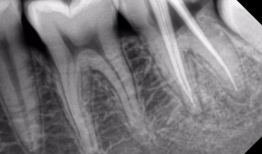

根管治疗视频,从视频学习根管治疗技巧与流程

最近是不是牙齿疼得你坐立不安,连笑容都变得苦涩了呢?别担心,今天就来给你揭秘一下那个听起来有点吓人的根管治疗,让你对这个过程有个...

2025-09-01 409